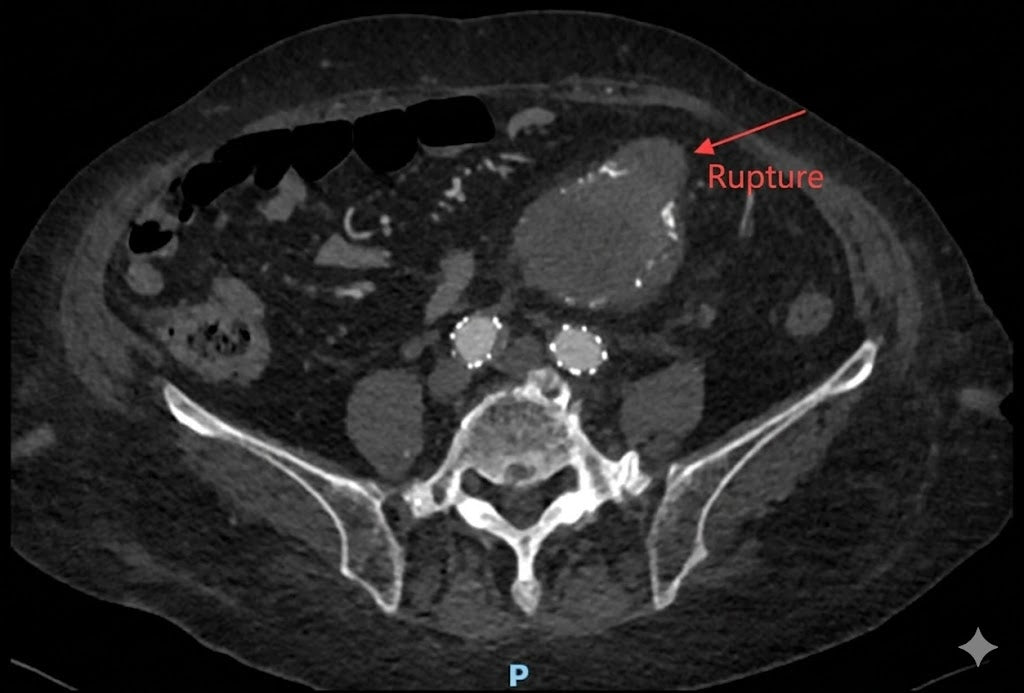

An 85-year-old patient with a history of emergency surgery for ruptured abdominal aortic aneurysm (AAA).

Presented with acute pain and a massive 120mm aneurysm. Complicated by systolic blood pressure over 200mmHg and extreme secondary rupture risks.